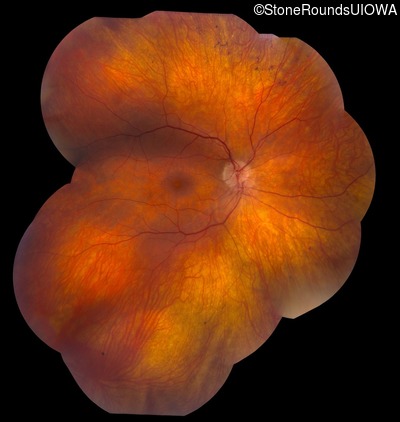

Fundus Montage - Right - 20/40 -2

Exemplar